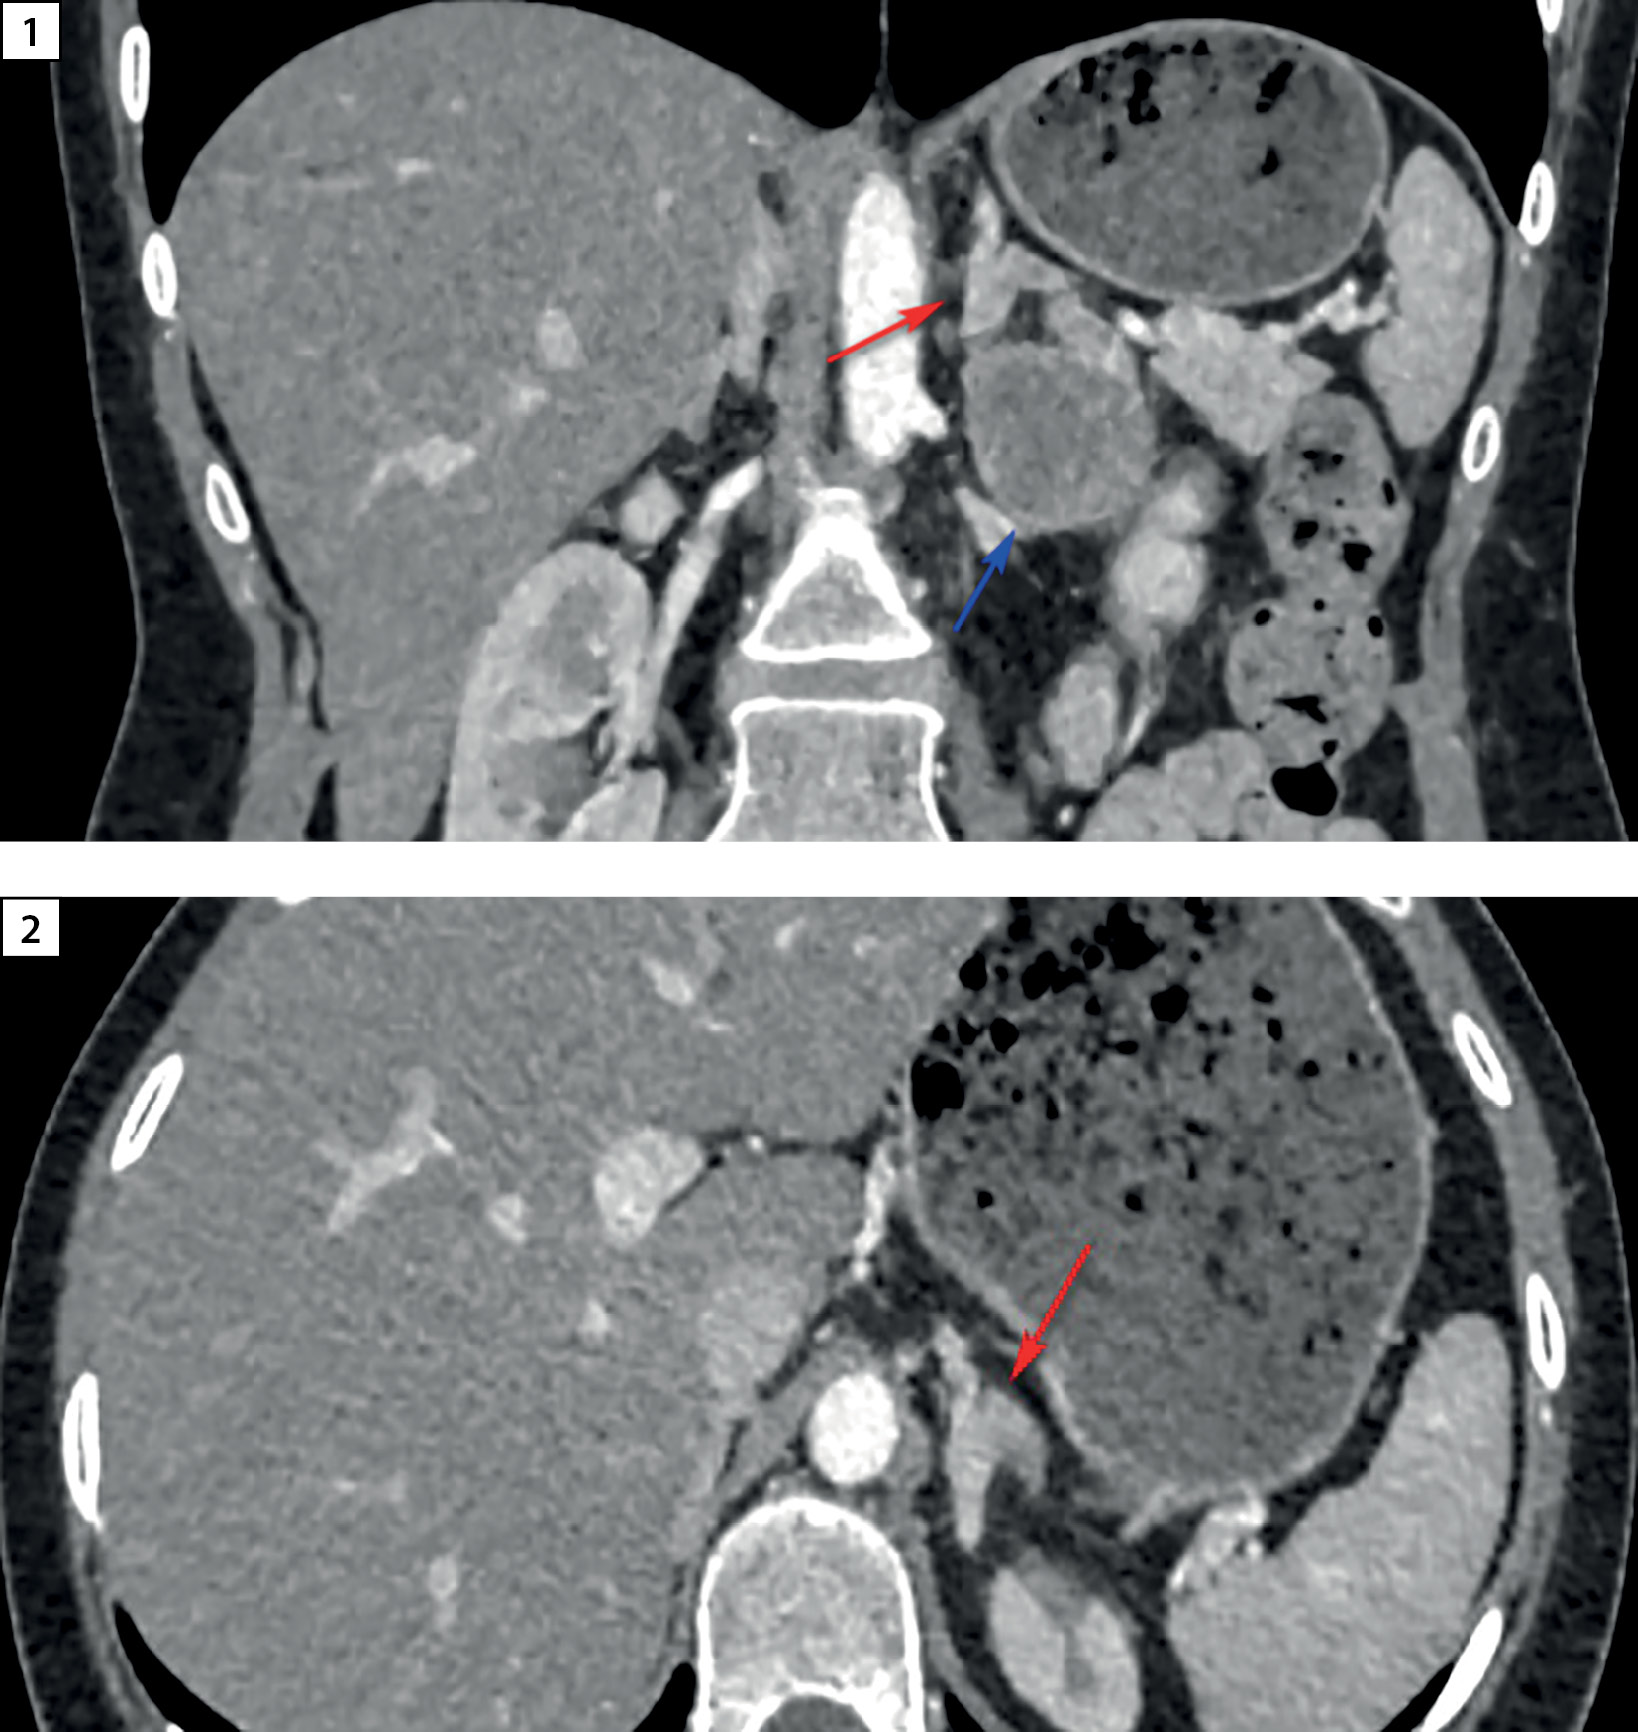

Дополнительно проведена сцинтиграфия с Тс-99-Тектротидом — на полученных планарных сцинтиграммах (всего тела) достоверных признаков патологического очагового накопления РФП не определялось. При ОФЭКТ-КТ брюшной полости и частично органов грудной клетки: из латеральной ножки левого надпочечника исходит образование мягкотканной плотности размерами 39х30х49 мм, накапливающее РФП, что подтвердило умеренно-повышенную экспрессию соматостатиновых рецепторов в объемном образовании левого надпочечника (рис. 3).

Рисунок 3. Соматостатин-рецепторная сцинтиграфия с Тс-99-Тектротидом

в режиме «все тело», стрелочками указано новообразование левого надпочечника.